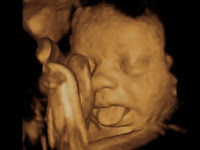

3d 4d Ultrasound Miami

Your 4d Baby 3d 4d Ultrasound Miami 10550 Nw 77th Ct 111

Pregnancy Ultrasound 3d 4d Doral Pembroke Pines